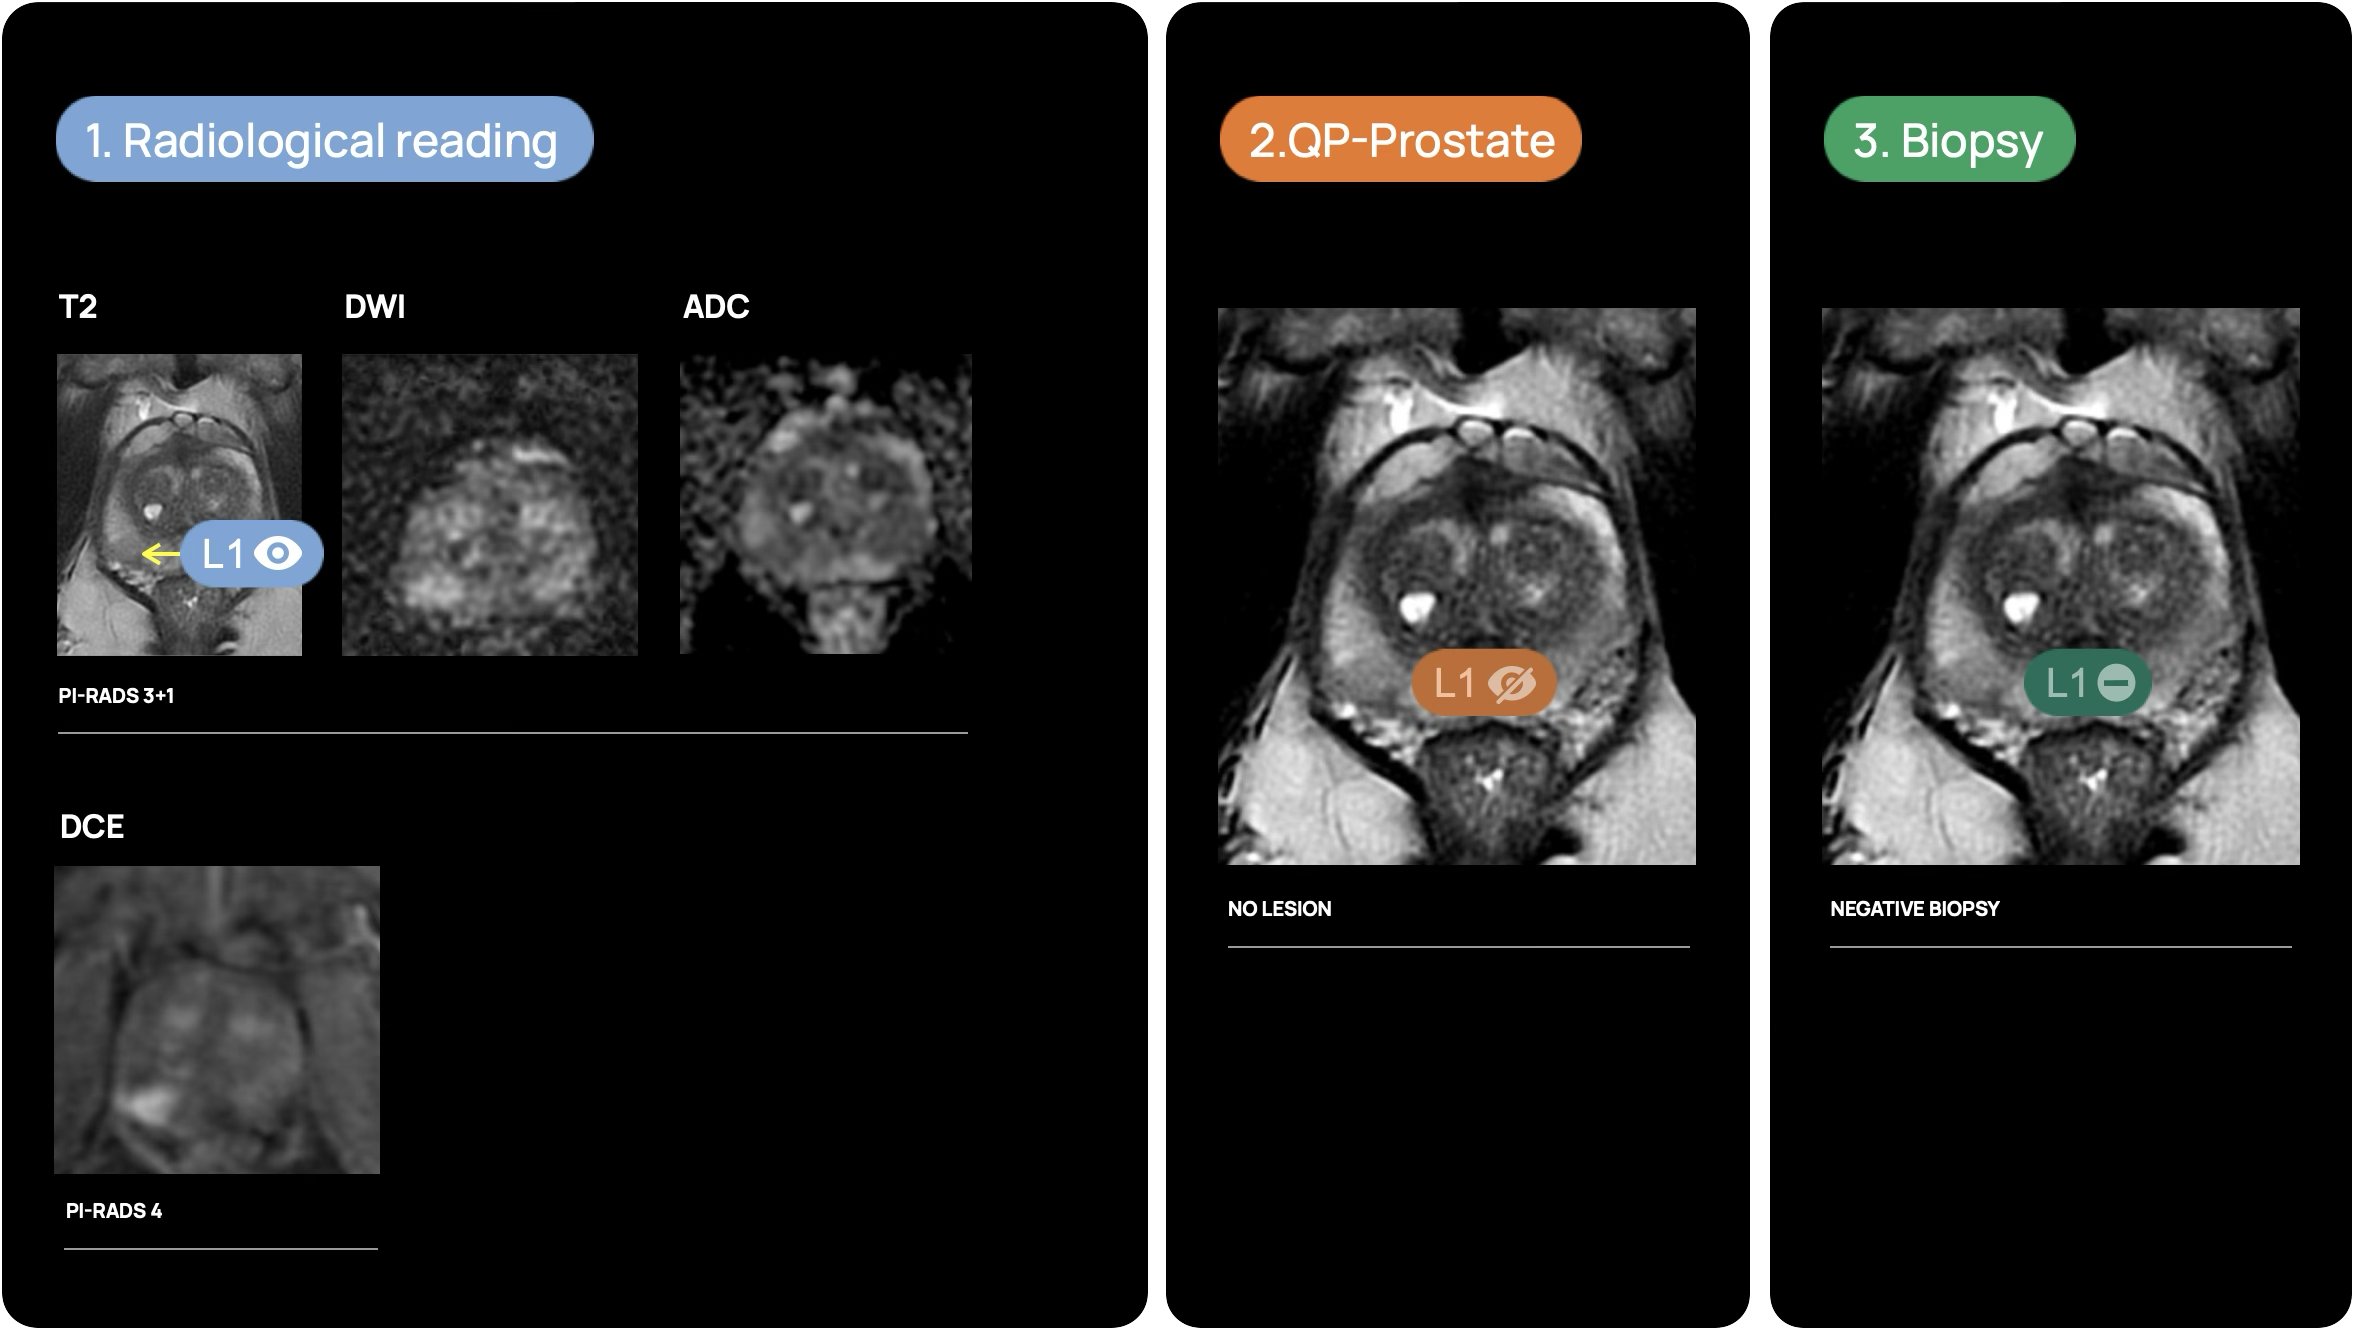

How does it work?

Changing the narrative in prostate diagnosis thanks to maximum accuracy in prostate MRI interpretation

In short, QP-Prostate leverages advanced artificial intelligence image processing techniques to offer a state-of-the-art approach to prostate MRI interpretation. This image processing software is compatible with standard workstations and allows for the visualization and analysis of DICOM data by qualified professionals.

Developed by Quibim, QP-Prostate excels in automating the segmentation of critical prostate regions, including the transition zone, peripheral zone and seminal vesicles. By streamlining these complex processes, the software not only aids in the interpretation of prostate MRI images, but also enables more accurate diagnoses. This combination of sophisticated AI-based analysis and user-friendly implementation makes QP-Prostate an invaluable tool in the hands of healthcare professionals, ensuring better patient outcomes through more reliable and detailed assessments.